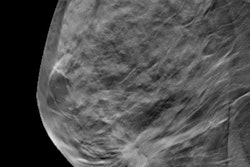

Calculations of breast density that are derived from digital breast tomosynthesis (DBT) exams may be more accurate than those derived from conventional 2D mammography in predicting cancer risk, according to research published September 14 in Radiology.

A team led by Aimilia Gastounioti, PhD, from the University of Pennsylvania created an algorithm that found fully automated volumetric estimates of breast density derived from DBT exams are more significantly associated with invasive breast cancer.

Assessing breast cancer risk is important for developing screening strategies for women, with previous research saying that breast density is a strong risk factor. Digital mammography has been the standard screening method, but DBT has been growing in popularity in recent years.

Researchers have touted DBT's ability to quantify dense breast tissue volumetrically by providing a quasi-3D image set. This in turn may result in more accurate breast density measures and improved breast cancer risk estimations. However, the potential of DBT for breast density has been unexplored, as volumetric breast density measures are only an approximation of the actual volume of dense tissue.

In the current study, the University of Pennsylvania team wanted to compare associations of breast density estimates derived from both DBT and digital mammography studies with rates of breast cancer diagnoses.